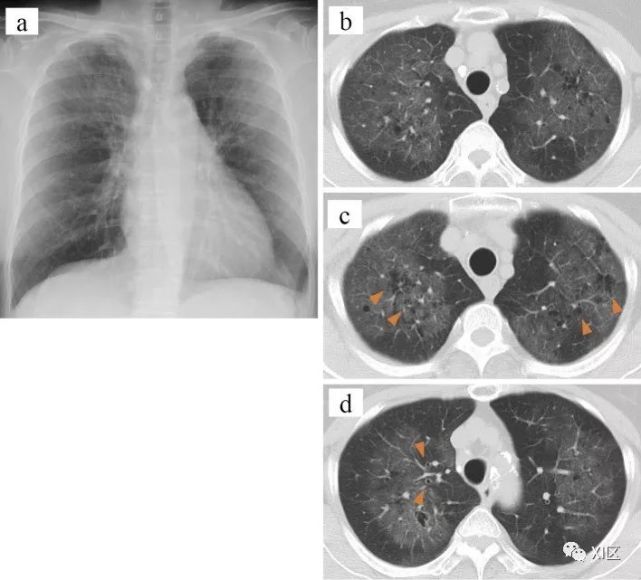

图15 27岁男性,HIV患者,高热三天。没有麻疹和免疫史。诊断为麻疹病毒肺炎。入院第11天的胸部CT图像显示双侧异常,包括小叶间隔增厚(肺尖部;B,箭)、支气管壁厚、多发大小不等的结节(分叉部;C,箭)、胸膜增厚(基底部;D,箭),以及弥漫性毛玻璃影,而第8天的胸片显示左肺出现毛玻璃影(A)。麻疹相关性肺炎的明确诊断基于三项发现:(1)体检发现;(2)微生物测试结果;和(3)典型的CT表现。

Takahashi T , Iwamoto A . Measles Pneumonia: Instructive Images by Chest Computed Tomography[J]. Journal of Experimental & Clinical Medicine, 2014, 6(2):72-73.